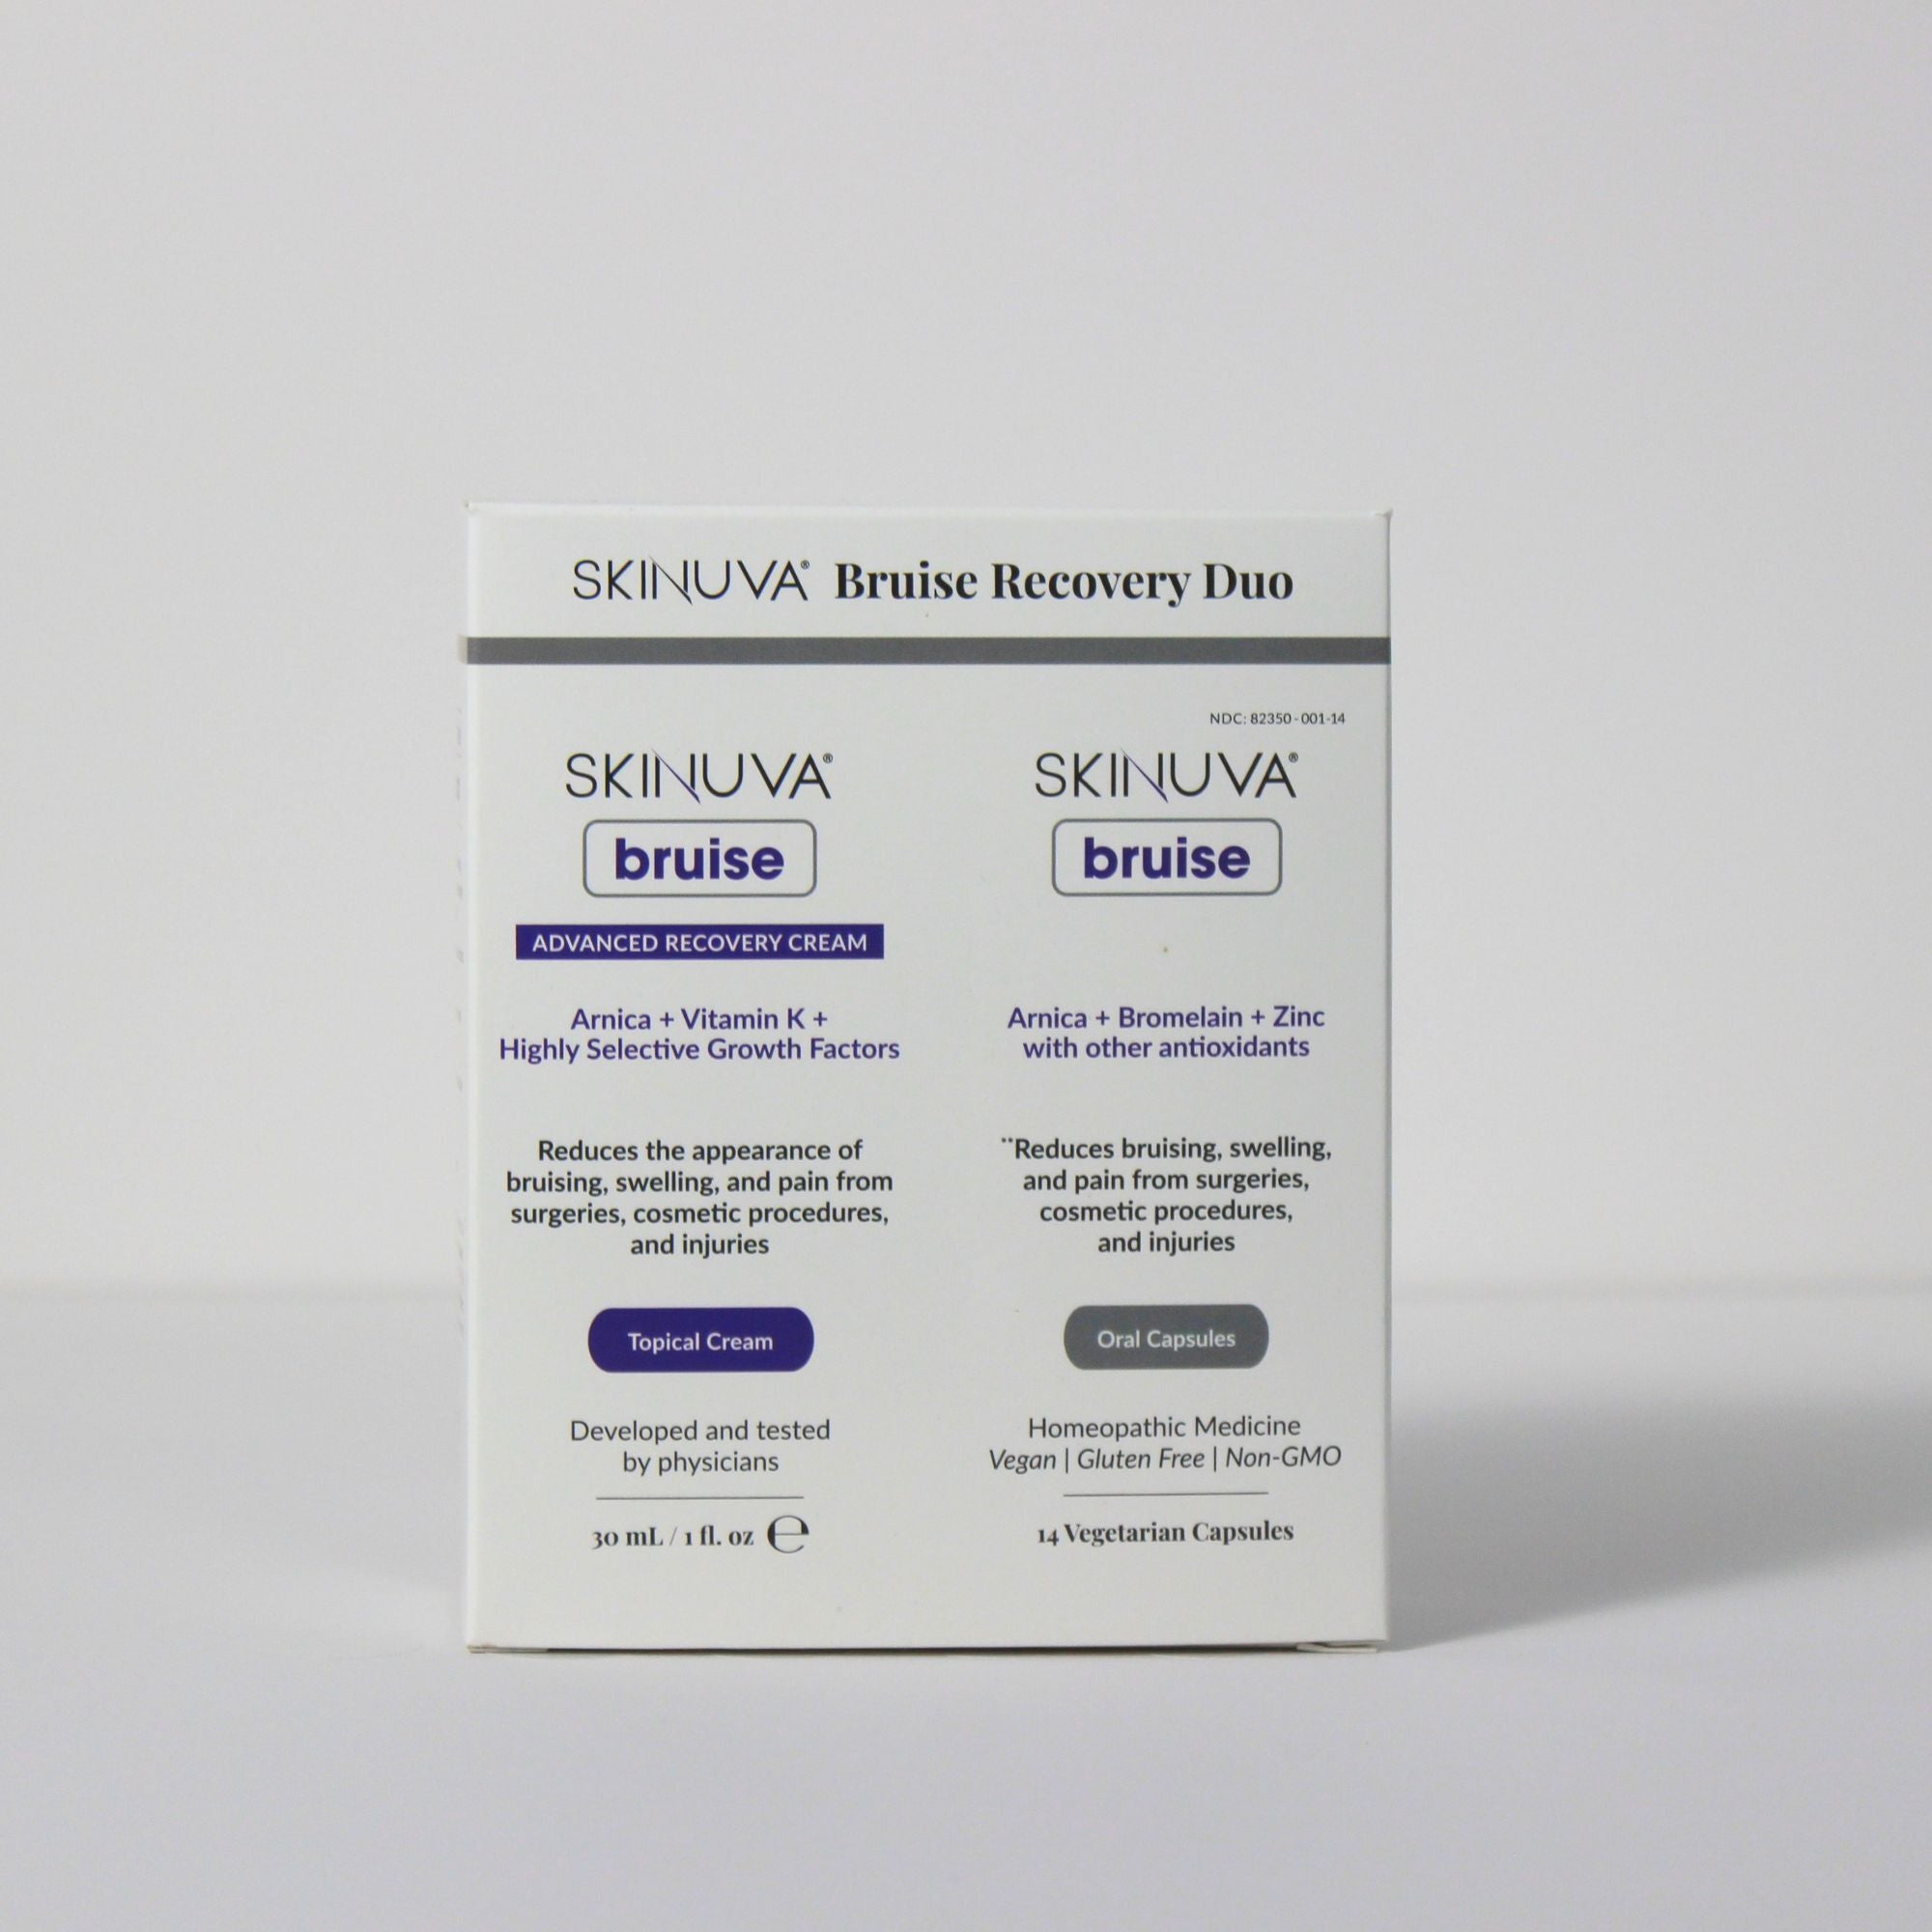

Using Skinuva Brite for Acne Scars and Post-Inflammatory Hyperpigmentation

If you are looking to treat certain types of acne scars or PIH, Skinuva Brite can be used twice daily, morning and night. Skinuva Brite is our physician developed, clinically tested, and non-hydroquinone skin brightening cream that contains Niacinamide. Backed by a published clinical study and with other scientific ingredients such as synthetic Growth Factors, Tranexamic Acid, Vitamin C, and Arbutin, Skinuva Brite not only helps improve PIH, but other types of hyperpigmentation such as melasma, sunspots, and more.